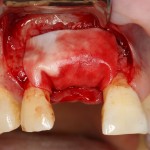

Другой вариант. Имплантируем, но существующего объема костной ткани недостаточно для получения адекватного эстетического и функционального результата:

Поэтому мы используем мембрану Geistlich BioGide и всё ту же аутокостную стружку: